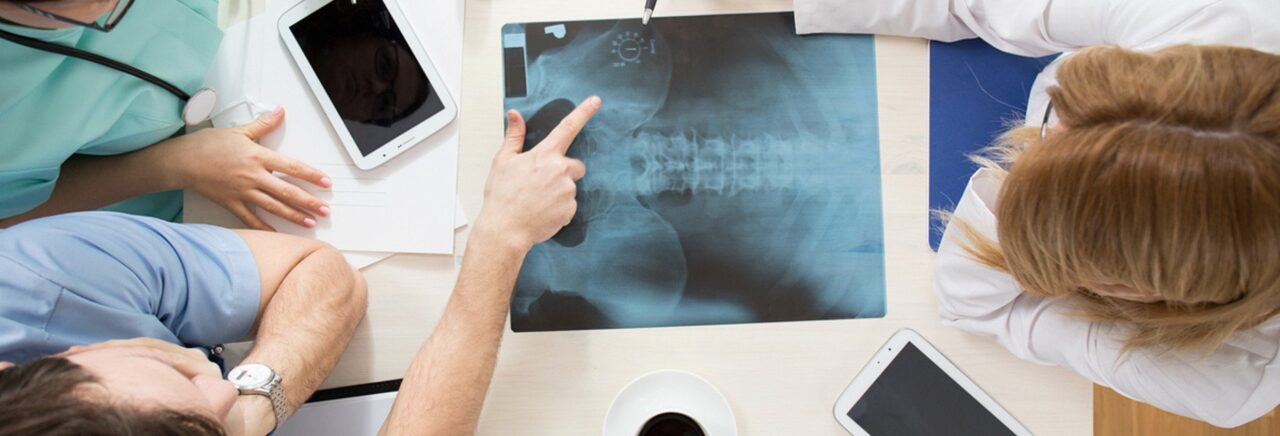

Why Rothman?

The joint replacement team at Rothman Orthopaedic Institute performs more than 9,000 surgeries every year. Each member of the team is specially trained, has extensive experience and is skilled to perform total joint replacements. Every physician that is a part of this outstanding team of doctors has undergone extensive subspecialty training during his/her residency and fellowship. This team is at the cutting edge of new research in the joint replacement field and Rothman physicians are actually responsible for training other orthopaedic surgeons through international lectures, webcasts, and surgical satellite simulcasts.